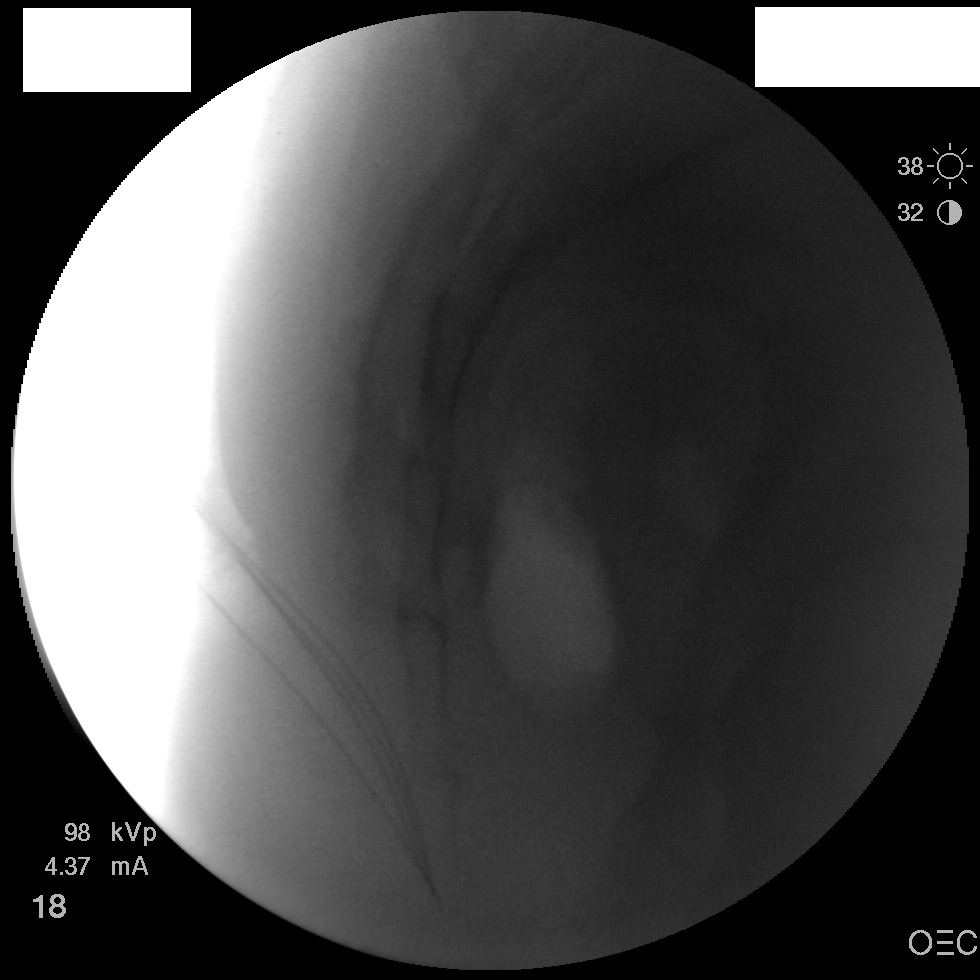

I have a patient with several months of coccyx pain. Worse with sitting, TTP over coccyx. Otherwise normal exam. No trauma, but she has an anteriorly displaced coccyx. Failed NSAIDs and no one around me does good pelvic floor PT. I scheduled her for ganglion impar injection, but her insurance won't pay for it. They wouldn't even let me to a peer-to-peer... they just straight up said they won't cover it. Any other treatment options? I don't want to send her to a surgeon. Thanks.